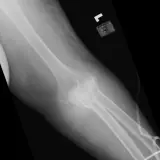

Over 2,100 interactive radiology cases, curated by radiologists for your level of training. Scroll, window, and view cases full screen โ€” just like on PACS. Click linked findings in each writeup to jump straight to them on the image. Cases include sample reports, a focused discussion section, original illustrations, and videos.

Casi completamente interattivi con gli strumenti che ti aspetti su un PACS: scroll, windowing, zoom, pan, misurazioni, ROI e modalitร  a schermo intero.

Annotazioni dettagliate evidenziano i reperti chiave direttamente sui casi. Clicca sui reperti collegati nella descrizione del caso per saltare alla loro esatta posizione sullo scan.